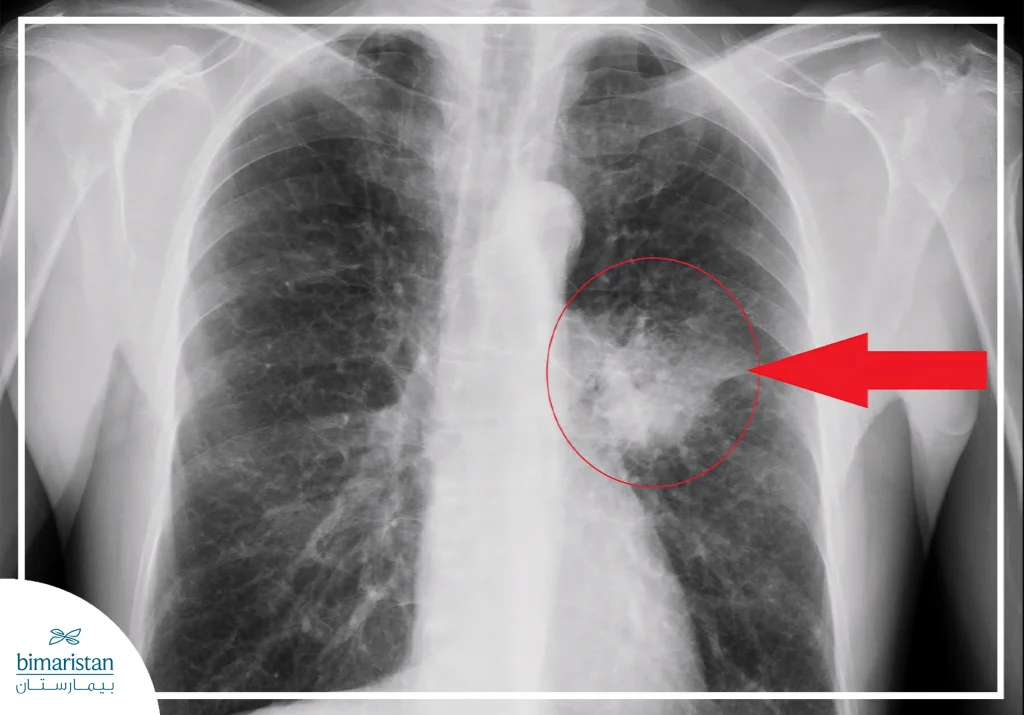

These signs may be mild or nonspecific in the early stages, making diagnosis a challenge that requires careful testing and a chest x-ray to confirm the presence of a tumor.

In many cases, lung adenocarcinoma is discovered accidentally during a chest X-ray for reasons unrelated to cancer. The X-ray image may show an indistinct shadow or an abnormal area of lung tissue. Although radiography is a useful initial tool, about a quarter of lung cancer cases may not be detected by X-ray alone, requiring more accurate tests to confirm the diagnosis.

- Chest X-ray: Used as an initial test, but may not show small or peripheral tumors.